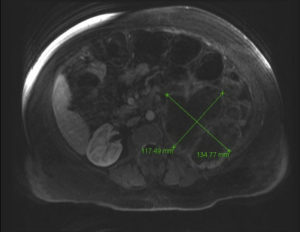

Обязательно проводят магнитно-резонансную или компьютерную томографию и УЗИ больной почки, а также кровеносных артерий, находящихся в брюшной полости. Пациенту необходимо заранее сделать флюорографию.